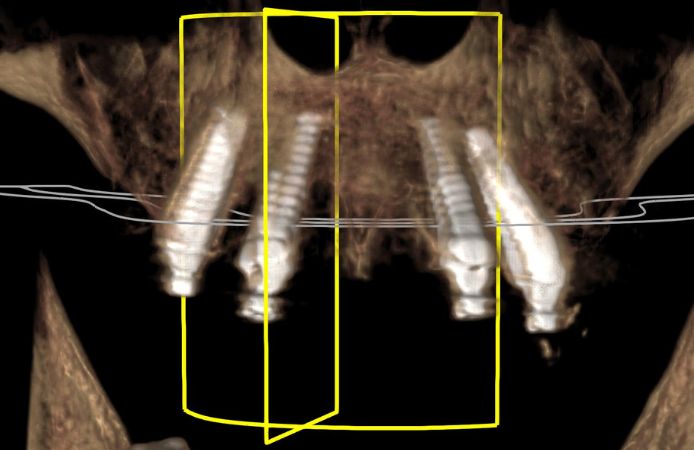

Figure 14.

CBCT image showing implant positions and re-angulation with Multi-Unit Abutments to achieve parallel prosthetic platforms.